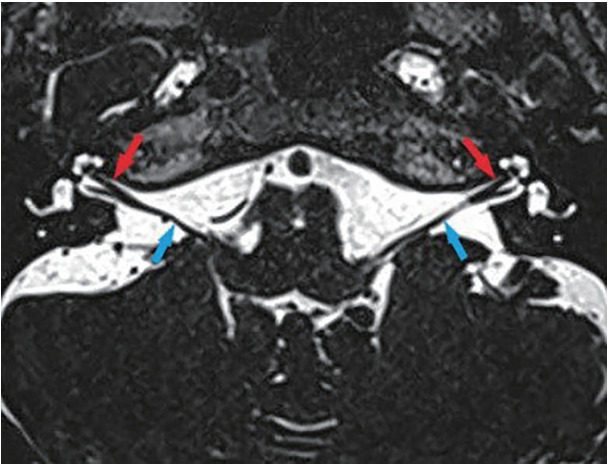

Abstract Image